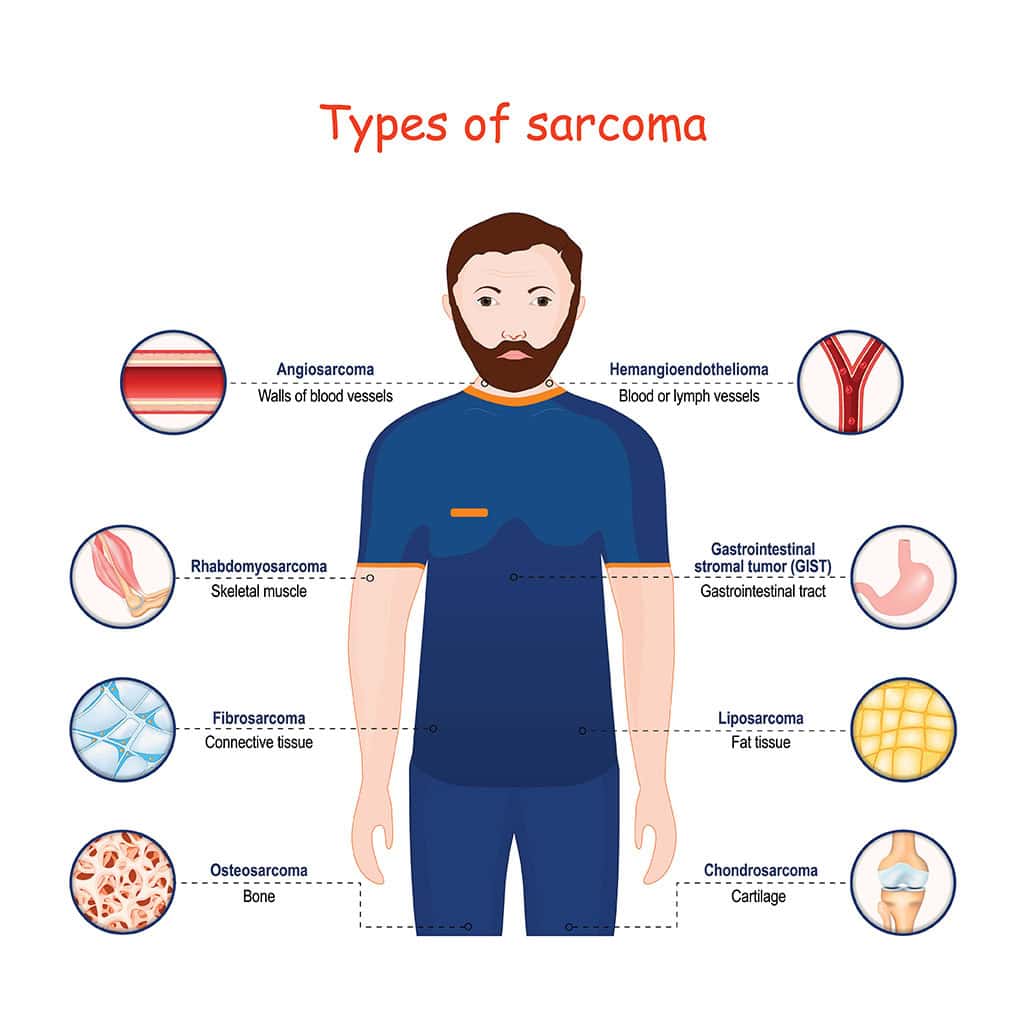

Other Names For Soft Tissue Sarcoma

Other Names For Soft Tissue Sarcoma

https://seankarlfoundation.org/wp-content/uploads/sarcoma-types.png